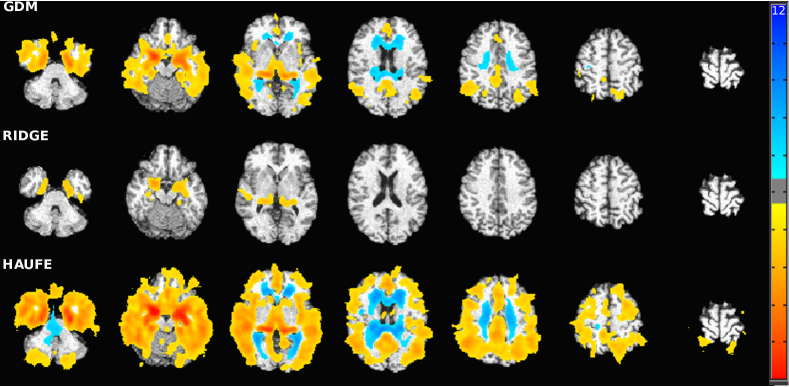

Statistical maps and p-values

To qualitatively assess and explain the predictive performance of the compared methods for the AD vs. CN scenario, we computed the model parameter maps using full resolution gray matter tissue density maps for the ADNI dataset (Fig. 4 top). Furthermore, since the null distribution of GDM, as well as ridge regression, can be estimated analytically, we computed p-values for the model parameters and displayed the regions surviving false discovery rate (FDR) correction [3] at level (Fig. 4 bottom).

The statistical maps demonstrated that both GDM and Haufe procedure yield patterns that accurately delineate the regions associated with AD, namely the widespread atrophy present in the temporal lobe, amygdala, and hippocampus. This is in contrast with the patterns found in ridge regression that resemble a hard to interpret speckle pattern with meaningful weights only on hippocampus. This once again confirmed the tendency of purely discriminative models to capture spurious patterns. Furthermore, the p-value maps of the Haufe method and ridge regression demonstrate the wide difference between features selected by generative and discriminative methods and how GDM strikes a balance between the two to achieve superior predictive performance.